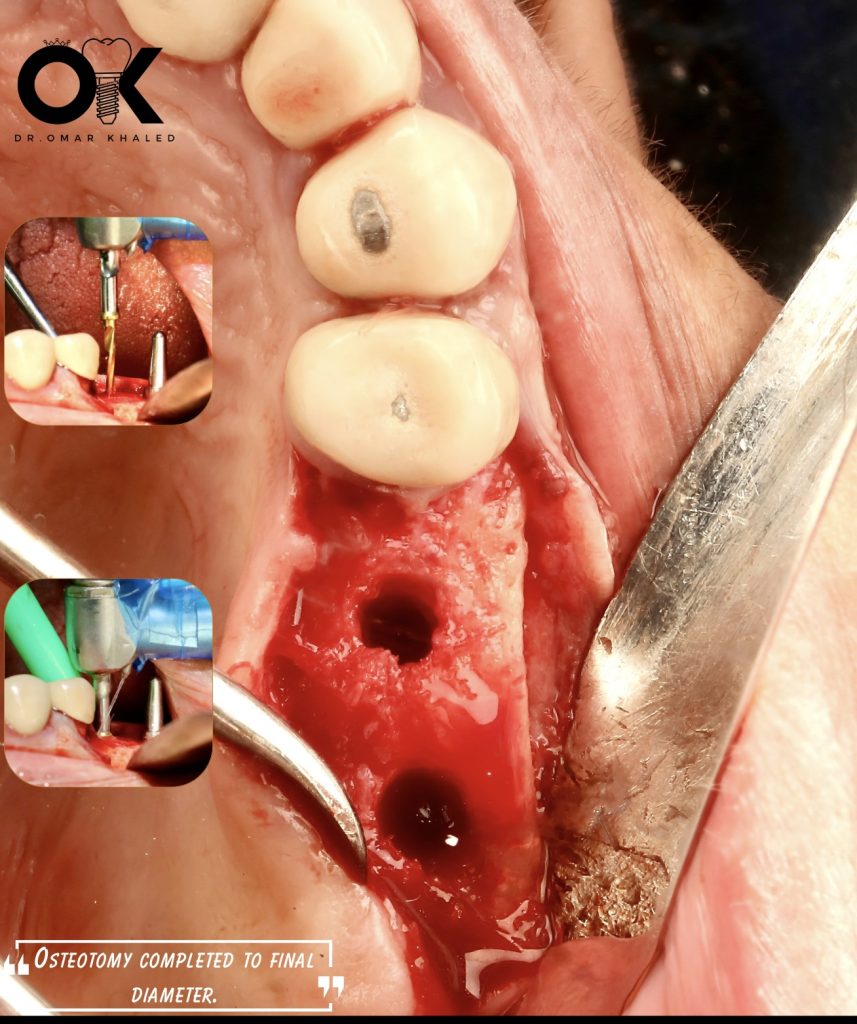

🦷 Site #15 & #16

🛠️ Megagen Surgical Kit

📍 Upper jaw, full sequence